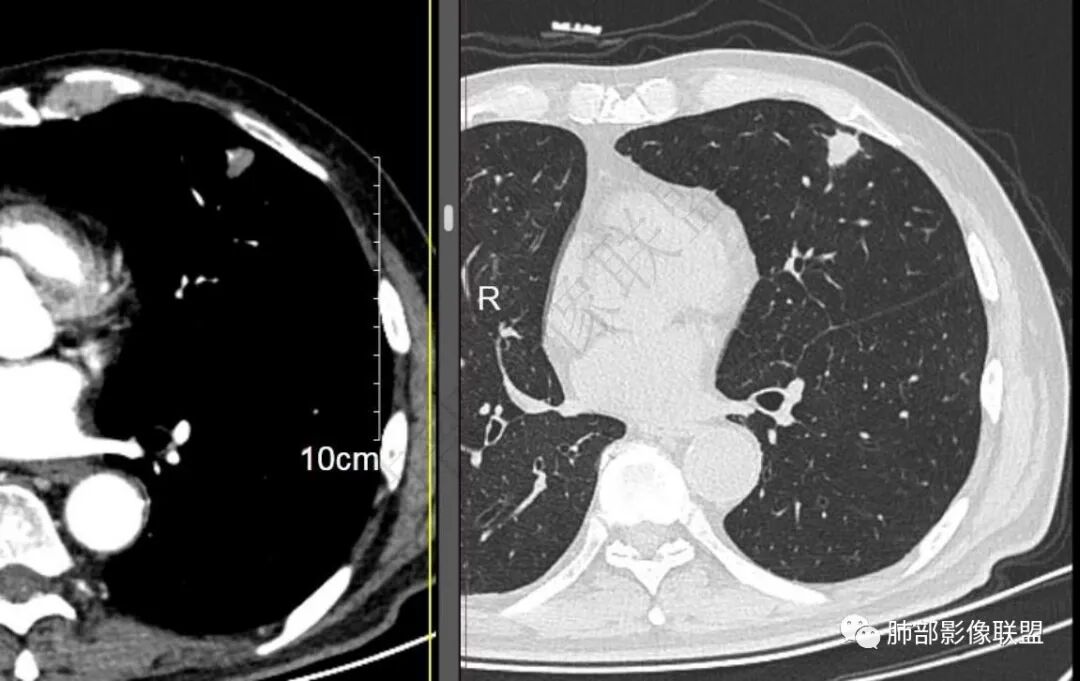

二..发现左肺上叶舌段实性密度小结节影,不规则略呈半环形,边界清楚,未见分叶、毛刺及磨玻璃晕。未见卫星病灶。

9个月后病灶明显增大,边缘较平直,部分膨隆,锁扣样外观,仍旧缺乏典型深分叶及张力,未见胸膜凹陷。

再1个多月后病灶继续增大,较明显不均匀强化,肺门一侧见低密度区。病灶边缘相对不清,可见毛刺。